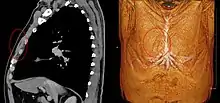

- Musculus sternalis seen at axial CT and volume rendering.